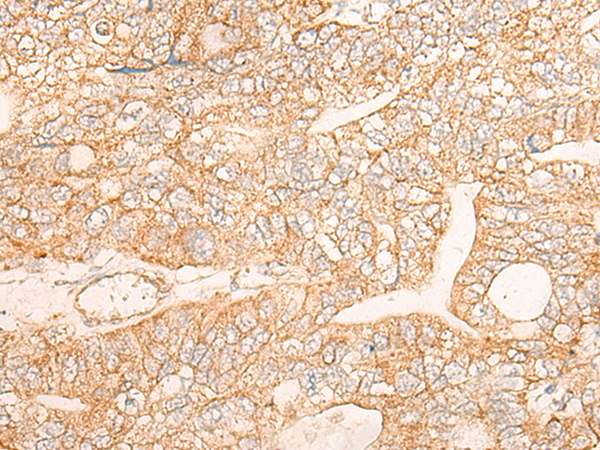

IHC positive control: |

Human liver cancer and Human gastric cancer |

IHC Recommend dilution: |

30-150 |